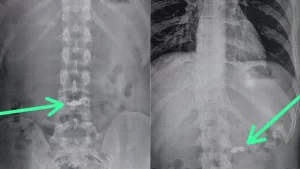

Um homem, de 20 anos, engoliu uma correntinha de ouro que foi furtada por ele na avenida Professor Alfredo Balena, no bairro Santa Efigênia, na